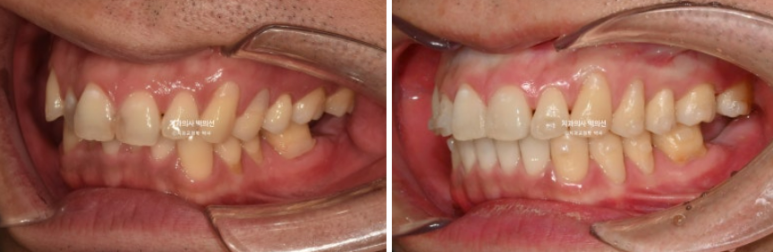

특히 파란 화살표 공간은 뒤 사랑니가 앞으로 많이 쓰러져서 임플란트가 힘든 상황입니다.

이렇게 좁아져버린 임플란트 공간을 회복하기 위해 쓰러지고 내려온 주변치아들을 정돈하는 교정을 보철교정이라고 합니다.

쓰러진 큰어금니를 세워 좁아진 임플란트 공간을 2mm 가량 더 확보했습니다.

배열도 개선이 많이 되었습니다.

24.05~25.03